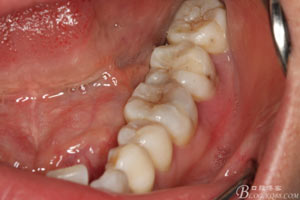

圖2.37牙冠基本完好,松動(dòng)Ⅰ度。合面有一開(kāi)髓孔被棉球覆蓋,頰側(cè)牙齦輕度紅腫。